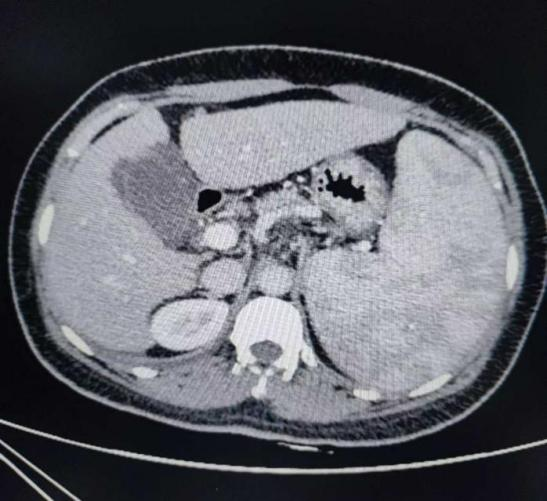

据南溪山医院肝胆胰脾外科副主任杨志坚介绍,脾切除术既属于治疗手段,又属于预防手段。一方面去除了肿大的脾脏以消除脾功能亢进,另外方面又离断了食管胃脾区的门体侧支以预防食管胃底静脉曲张出血。腹腔镜手术因巨脾占位效应,导致手术操作空间狭小,加之脾脏血管异常扩张,血管变薄极易造成大出血导致手术失败,对手术医生要求较高。相比开放手术,腹腔镜下手术的切口面积小,创伤少,有助于缓解疼痛降低机体炎性反应,对患者免疫力影响较小。腹腔镜操作模式下,患者肠管内部环境稳定术中不会对肠管产生严重挤压,有助于病情短时间内恢复。

蒋女士腹部伤口

传统开腹伤口